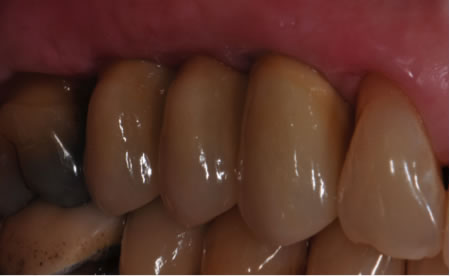

After Immediate Implants, bone graft and soft tissue graft – the full contour of the ridge is repaired, and restored with a new porcelain bridge